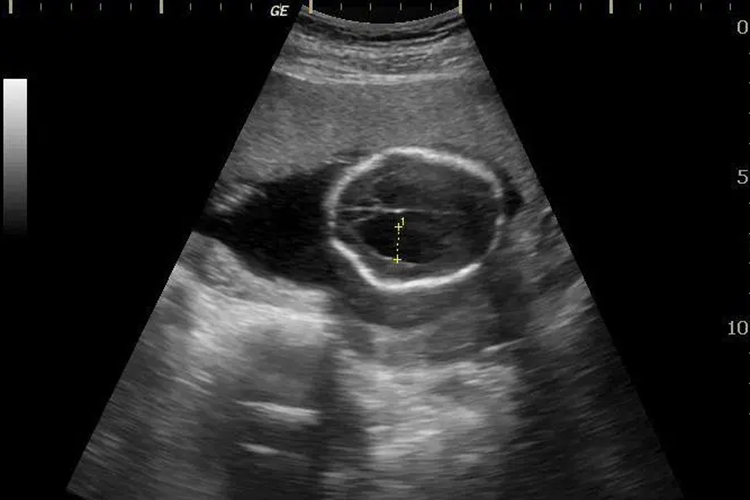

大排畸通常在妊娠20-24周时进行的胎儿系统超声检查,筛查胎儿结构畸形。正常情况下胎儿心、脑、肾、膀胱、胃、上唇、四肢骨、脊柱、腹壁等均正常。当出现侧脑室增宽、脊柱椎弓间距增宽、软腭裂、双肾增大、心脏增宽、裂腹畸形伴肠管外翻等异常情况时,多提示胎儿发育异常。